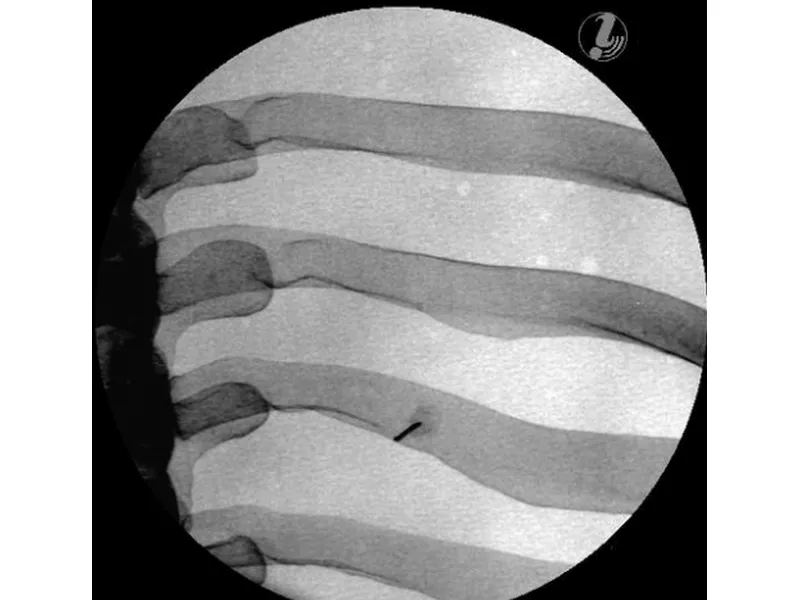

Тренажер для спинальных инъекций в грудную клетку под визуальным контролем

Тренажер для отработки инъекций в грудной отдел с визуальным контролем позволяет обучаемым выработать пространственное представление о порядке выполнения процедуры с целью успешного проведения медицинского вмешательства на позвоночнике. Они смогут научиться соотносить анатомию грудного отдела позвоночника с соответствующими интервенционными обезболивающими процедурами, определять целевую ткань и легко повреждаемые структуры с помощью визуализации и анатомического обследования, а также применять передовые методы для обеспечения безопасности пациента при проведении интервенционных процедур на позвоночнике.

Манекен для инъекций имеет анатомически точную костную структуру (позвонки T3-T8, ребра 3-8) и реалистичную тактильную обратную связь в ходе практики. Кроме того, он выполнен из самовосстанавливающегося материала, который позволяет многократно использовать тренажер.